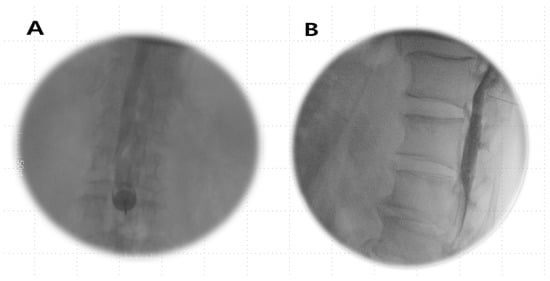

The anatomical characteristics of the subdural space give rise to varied imaging patterns, ranging from “railroad track” images to dense “sausage-like mass” contrasts. However, the lack of universally accepted diagnostic criteria for subdural injection stems from the nonexistent nature of the subdural space, which arises from iatrogenic fissures. The complexities of the epidural space go beyond initial recognition [6,18]. The contrast media patterns in epidural anesthesia exhibit variability owing to factors such as anatomical variations in the epidural space, the dynamics of the injectate flow, the expertise of anesthesiologists, and the nature and extent of spinal pathology [7]. Occasionally, epidural pooling and indentation during contrast-enhanced anesthesia may mimic a subdural pattern [12], particularly when a small volume of contrast-enhanced anesthetic is administered [6]. The most difficult aspect for us to distinguish was between epidural pooling, thick epidural spread, and subdural contrast images. Over time, epidural pooling contrast images undergo dilution and transform into outermost linear, thin anterior, and/or posterior epidural images (Figure 6A,B), whereas subdural contrast images remain unchanged over time, without dilution, and their shape remains constant. It was according to these time-dependent changes in the images that we were able to make some determinations. Additionally, based on our empirical knowledge, patients with epidural, subdural, or combined epidural–subdural imaging patterns report significant radiating leg pain upon injection. In contrast, those with combined subdural–subarachnoid or subarachnoid-only imaging patterns mainly complained of tingling sensations in their legs. Consequently, the patient symptoms during contrast-enhanced anesthesia injection and time-dependent changes in radiocontrast imaging proved valuable in identifying the injected space.

Figure 6.

Changes in epidural images over time. (A) Immediate after epidural anesthesia: epidural pooling phase. (B) 10 min after epidural anesthesia: outermost linear, thin anterior, and/or posterior epidural images.